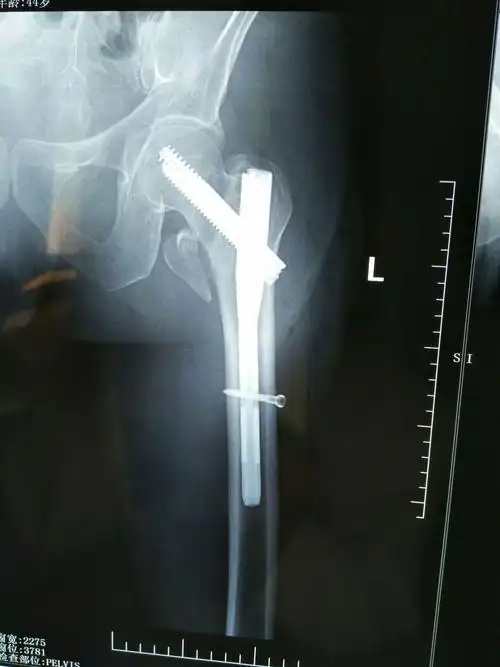

intertan髓内钉内固定病例分享(尧都区人民医院骨三科高峰)